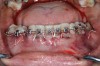

Fig 2. An abundant amount of bone biomaterial was placed during SFOT to compensate for anticipated graft shrinkage during healing.

Figure 2

Fig 3. Suturing after SFOT procedure; note the shallow vestibule post-closure.

Figure 3

Fig 4. A slight dehiscence of the flap was noted postoperatively. The prominent symphysis and associated strain of the mentalis muscle pull may have played a role in compromised soft-tissue healing.

Figure 4